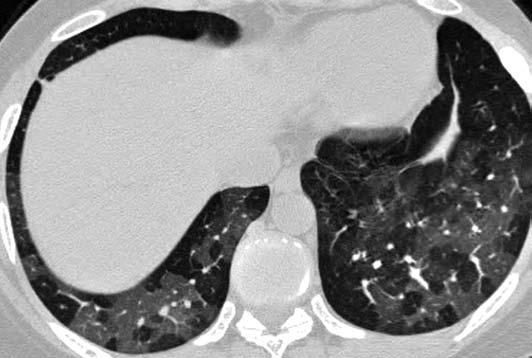

HRCT may be more sensitive than pulmonary function tests for detecting small-airways disease, and it frequently shows moderate to severe air trapping on expiratory images (Figure 1).9 Obstruction, hyperinflation, and air trapping can be demonstrated on pulmonary function testing, but both restrictive and obstructive physiology may be observed in later stages of disease.

Figure 1 – Bronchiolitis obliterans developed in a 32-year-old woman with rheumatoid arthritis. Transverse high-resolution CT image shows heterogeneous/ mosaic lung attenuation with multifocal air trapping (demonstrated on expiratory images).